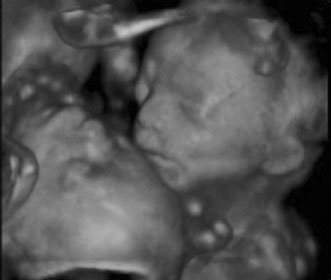

First trimester ultrasound may be performed transabdominally or transvaginally. Table 7 lists the components of a first trimester ultrasound. A crown–rump length, done between 7 and 13 weeks, can define a gestational age to within 5 days (Fig. 7).

Fig. 7. First trimester ultrasound showing crown–rump length.